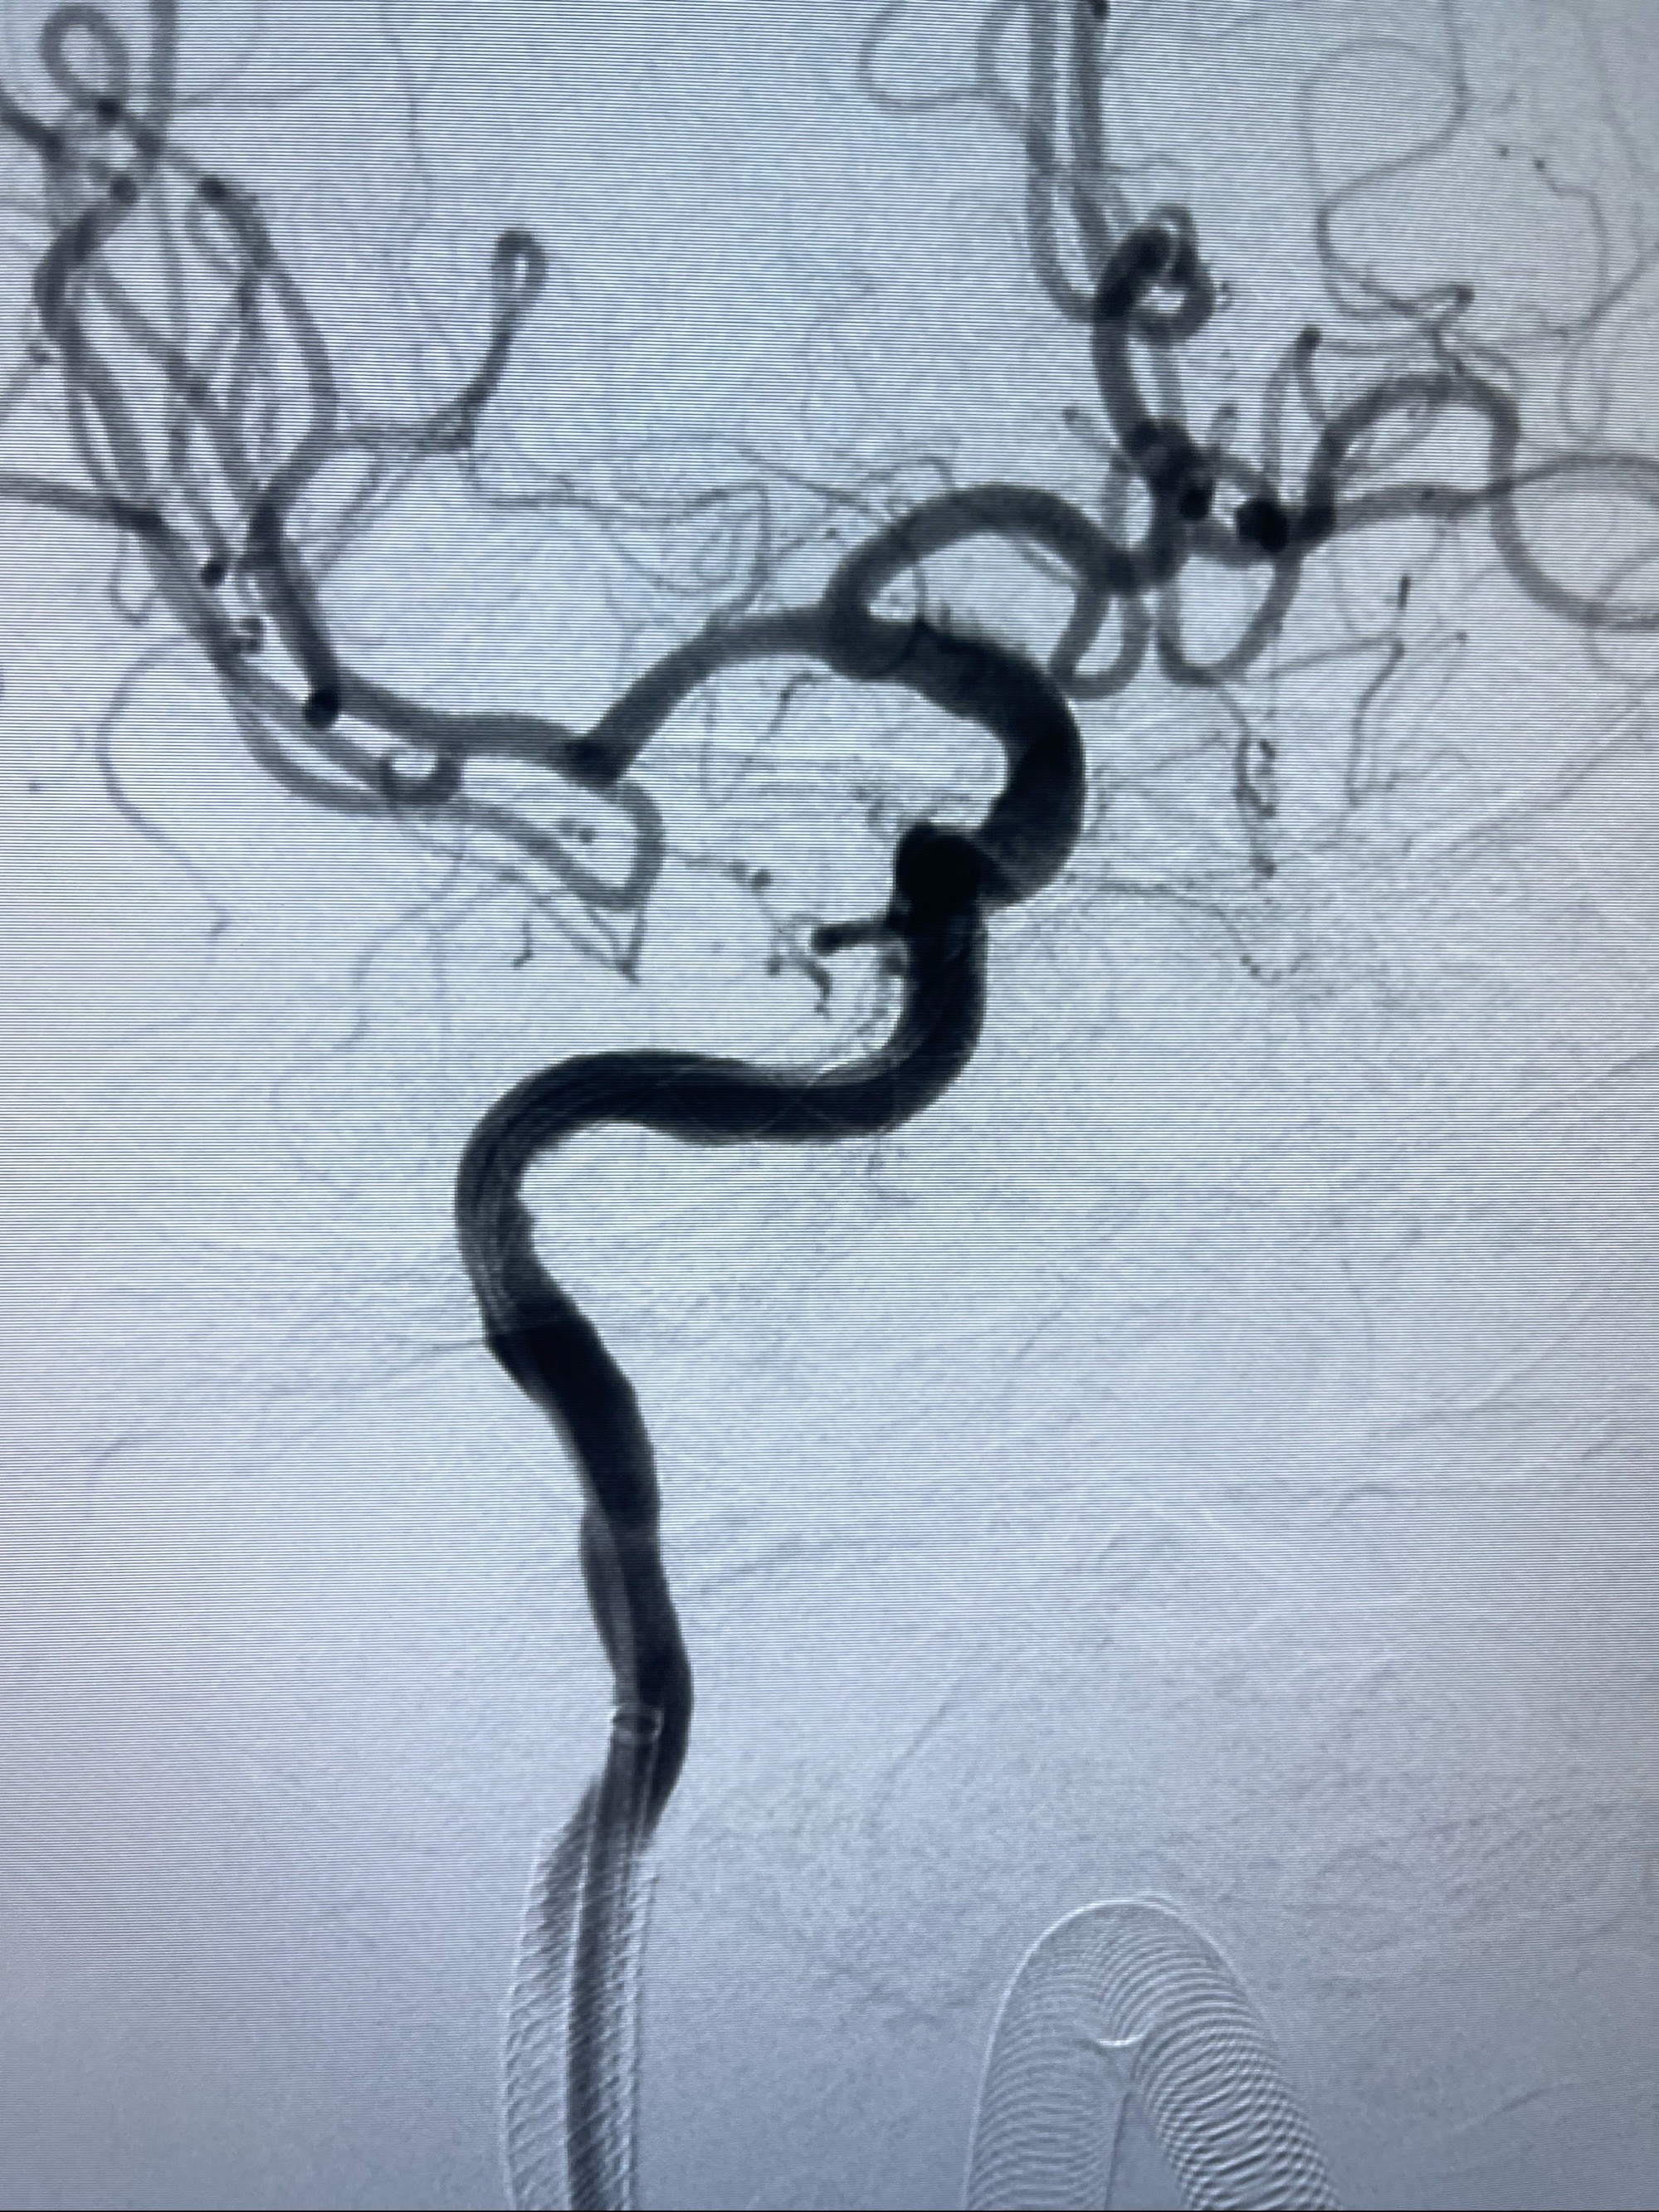

2023-07-10DSA:右侧颈内动脉岩骨段夹层伴中偏重度狭窄改变,左侧颈总动脉闭塞、右侧颈外动脉由右侧肋颈干甲颈干吻合代偿

箭头所示为颈内动脉岩骨段重度狭窄,结合MRI,考虑为肿瘤侵犯右侧颈内动脉

箭头以近至支架段管腔不规则狭窄

经导引导管造影显示支架远端颈内动脉不规则狭窄伴局部充盈缺损,同时行全身肝素化5ml